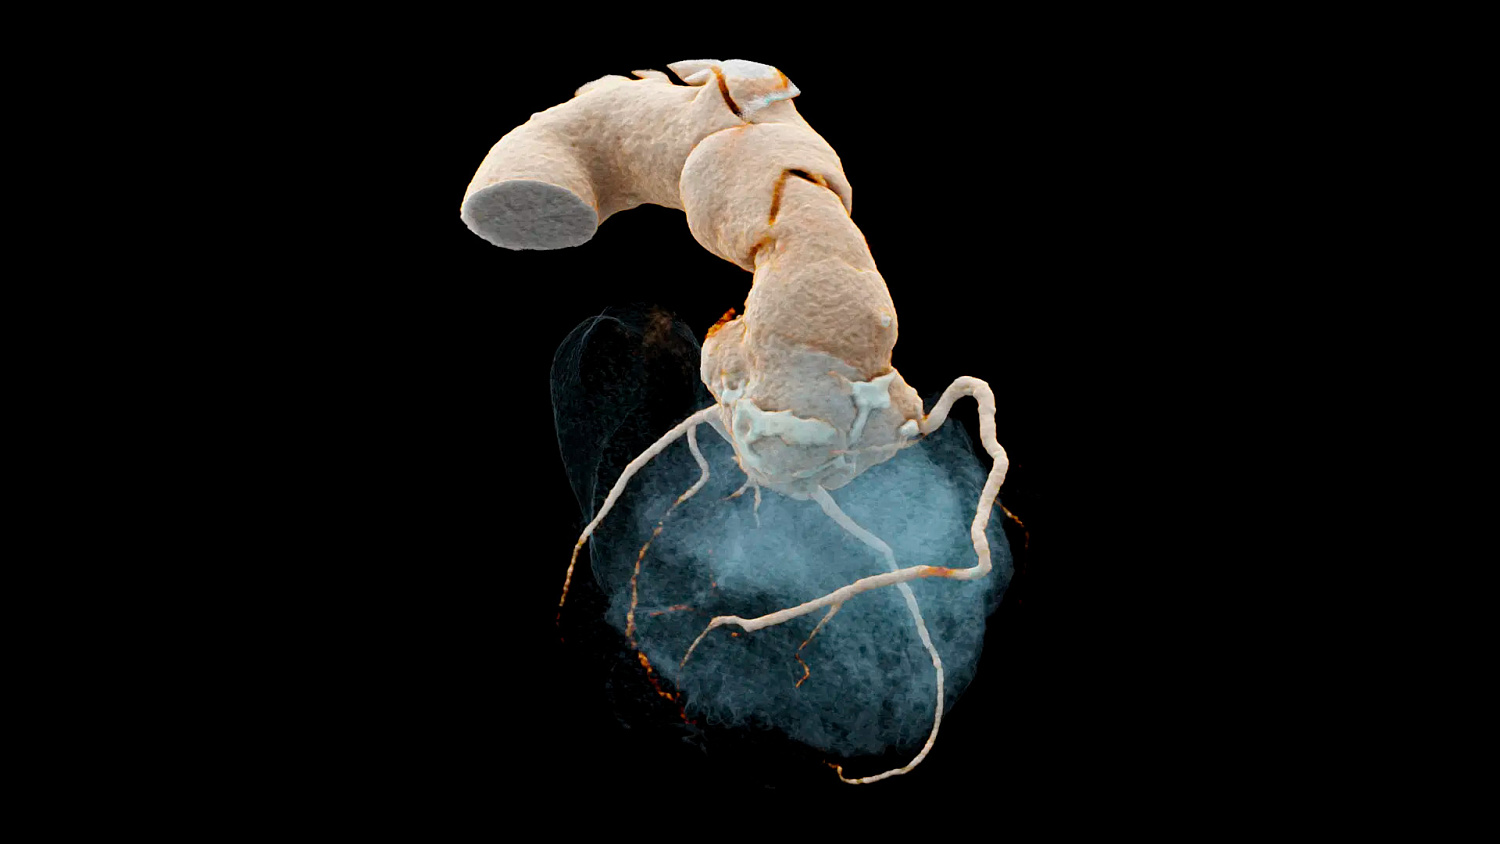

Квантовый HD для кардиологии

Сканирование сердца возможно при толщине среза до 0,2 мм. В сочетании с превосходным временным разрешением 66 мс и низким показателем дозы сканирования теперь позволяет выявить впечатляющие детали коронарных сосудов.